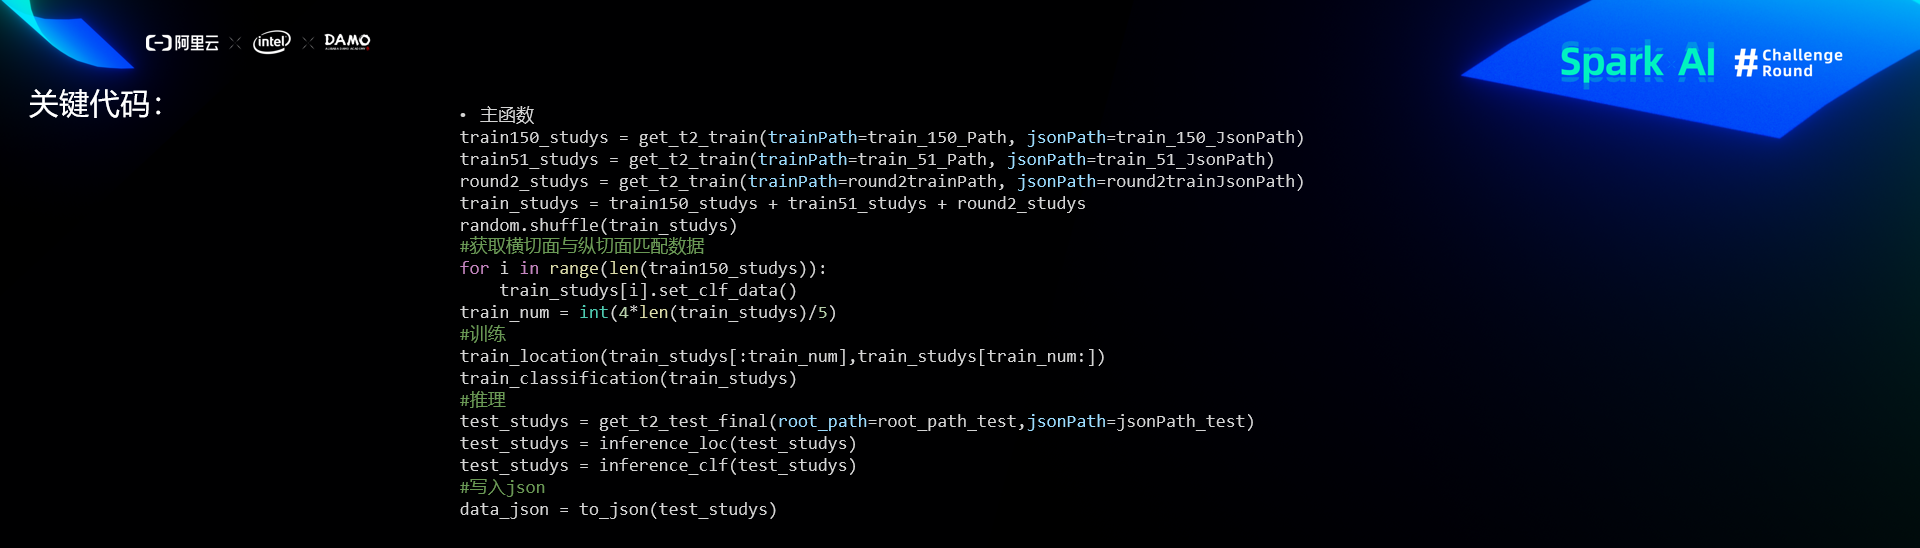

关键代码